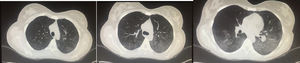

Association with high titers of anti-dsDNA antibodies has been described. The utility of bronchoalveolar lavage (BAL) lies in that it rules out infection; characteristically, there is an increase in cellularity at the expense of activated polymorphonuclear cells.3 The extraction of a biopsy specimen can be limited to cases of uncertain diagnosis for the exclusion of alternative etiologies. The findings are nonspecific: damage to the alveolar wall and necrosis, infiltration by inflammatory cells, edema, hemorrhage and hyaline membranes.16 A number of experts question the existence of this syndrome unless one or more of the following findings are demonstrated: interstitial fibrosis, vasculitis, hematoxylin bodies, interstitial pneumonitis, alveolitis or pleuritis.27 It is useful to remember that, in terms of the diagnosis, the establishment of lupus pneumonitis is nearly always simultaneous with a flare of the disease, in general with multiple organ involvement (e.g., renal involvement and serositis) and, in most cases, this occurs in the presence of anti-SSA antibodies (82%). Thus, the combination of pneumonitis with multiorgan involvement in a patient who is positive for anti-SSA supports the diagnosis.29Fig. 2 shows an example of a computed tomography from a patient with lupus pneumonitis.

A 24-year-old woman with a 4-year history of generalized lupus erythematosus characterized predominantly by musculoskeletal and hematological manifestations (autoimmune hemolytic anemia). She came to the emergency department with a 10-day history consisting of dyspnea and dry cough and later on with hemoptysis on 6 occasions. At admission, she had tachycardia and hypoxemia. Computed tomography revealed predominantly bibasal ground glass. After an infectious process was ruled out, the possibility of lupus pneumonitis was considered. She received pulses of methylprednisolone and cyclophosphamide and improvement was achieved.